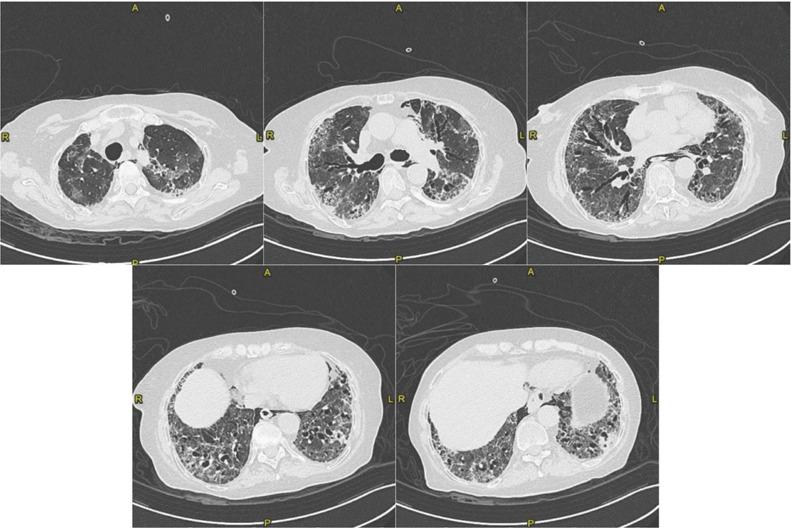

Platypnea-Orthodeoxia Syndrome (POS) is a clinical entity defined as positional dyspnoea (platypnea) and arterial desaturation (orthodeoxia) that occurs when sitting or standing up and usually resolves by lying down. Up to April 25th 2021, eleven cases of POS after SARS-CoV-2 pneumonia have been reported on Pubmed. Accordingly, SARS-CoV-2 infection may be considered as an emergent cause of POS due to an increase in ventilation/perfusion (V/Q) mismatch. In this article we provide an update on the patient with POS after fibrotic evolution of SARS-CoV-2 interstitial pneumonia, which we previously reported and we discuss the case reports of POS due to SARS-CoV-2 infection.

体位性呼吸困难-低氧血症综合征(POS)是一种临床病症,定义为当坐立或站立时出现呼吸困难(体位性呼吸困难)和动脉血氧饱和度降低(低氧血症),而当躺下时通常会缓解。截至 2021 年 4 月 25 日,在 Pubmed 上已报告了 11 例 SARS-CoV-2 肺炎后 POS 病例。因此,由于通气/血流(V/Q)不匹配增加,SARS-CoV-2 感染可被视为 POS 的一个新出现病因。在本文中,我们对先前报道的纤维化演变后的 SARS-CoV-2 间质性肺炎后出现 POS 的患者进行了更新,并讨论了因 SARS-CoV-2 感染而出现 POS 的病例报告。